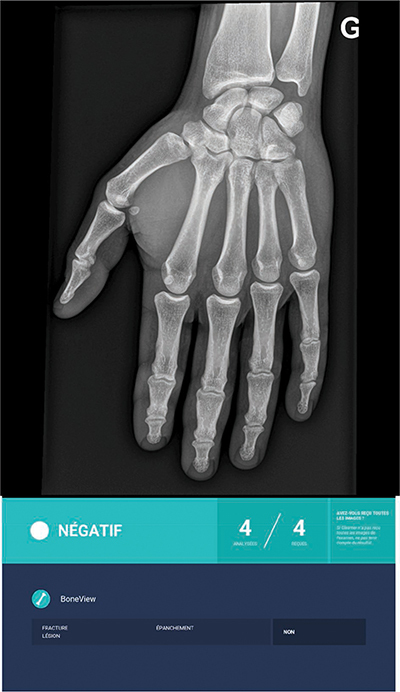

Objectives: The aims of this study were: (a) to evaluate the performance of an artificial intelligence (AI) software package (Boneview Trauma, Gleamer) for the detection of post-traumatic bone fractures in radiography as a standalone; (b) used by two radiologists (osteoarticular senior and junior); and (c) to determine to whom AI would be most helpful.

Materials and methods: Within 14 days of a trauma, 101 consecutive patients underwent radiographic examination of the upper or lower limbs. The definite diagnosis for identifying fractures was: (a) radio-clinical consensus between the radiologist on-call who analyzed the images and the orthopedist (Group 1); (b) Cone Beam computed tomography (CBCT) exploration of the area of interest, in case of doubts or absence of consensus (Group 2). Independently of this diagnosis for both groups, the radiographic images were separately analyzed by two radiologists (osteoarticular senior: SR; junior: JR) prior without, and thereafter with the results of AI.

Results: AI performed better than the radiologists in detecting common fractures (Group 1), but not subtle fractures (Group 2). In association with AI, both radiologists increased their overall performances in both groups, whereas this increase was significantly higher for the JR (p < 0.05).

Conclusion: AI is reliable for common radiographic fracture identification and is a useful learning tool for radiologists in training. However, the software's overall performance does not exceed that of an osteoarticular senior radiologist, particularly in case of subtle lesions.